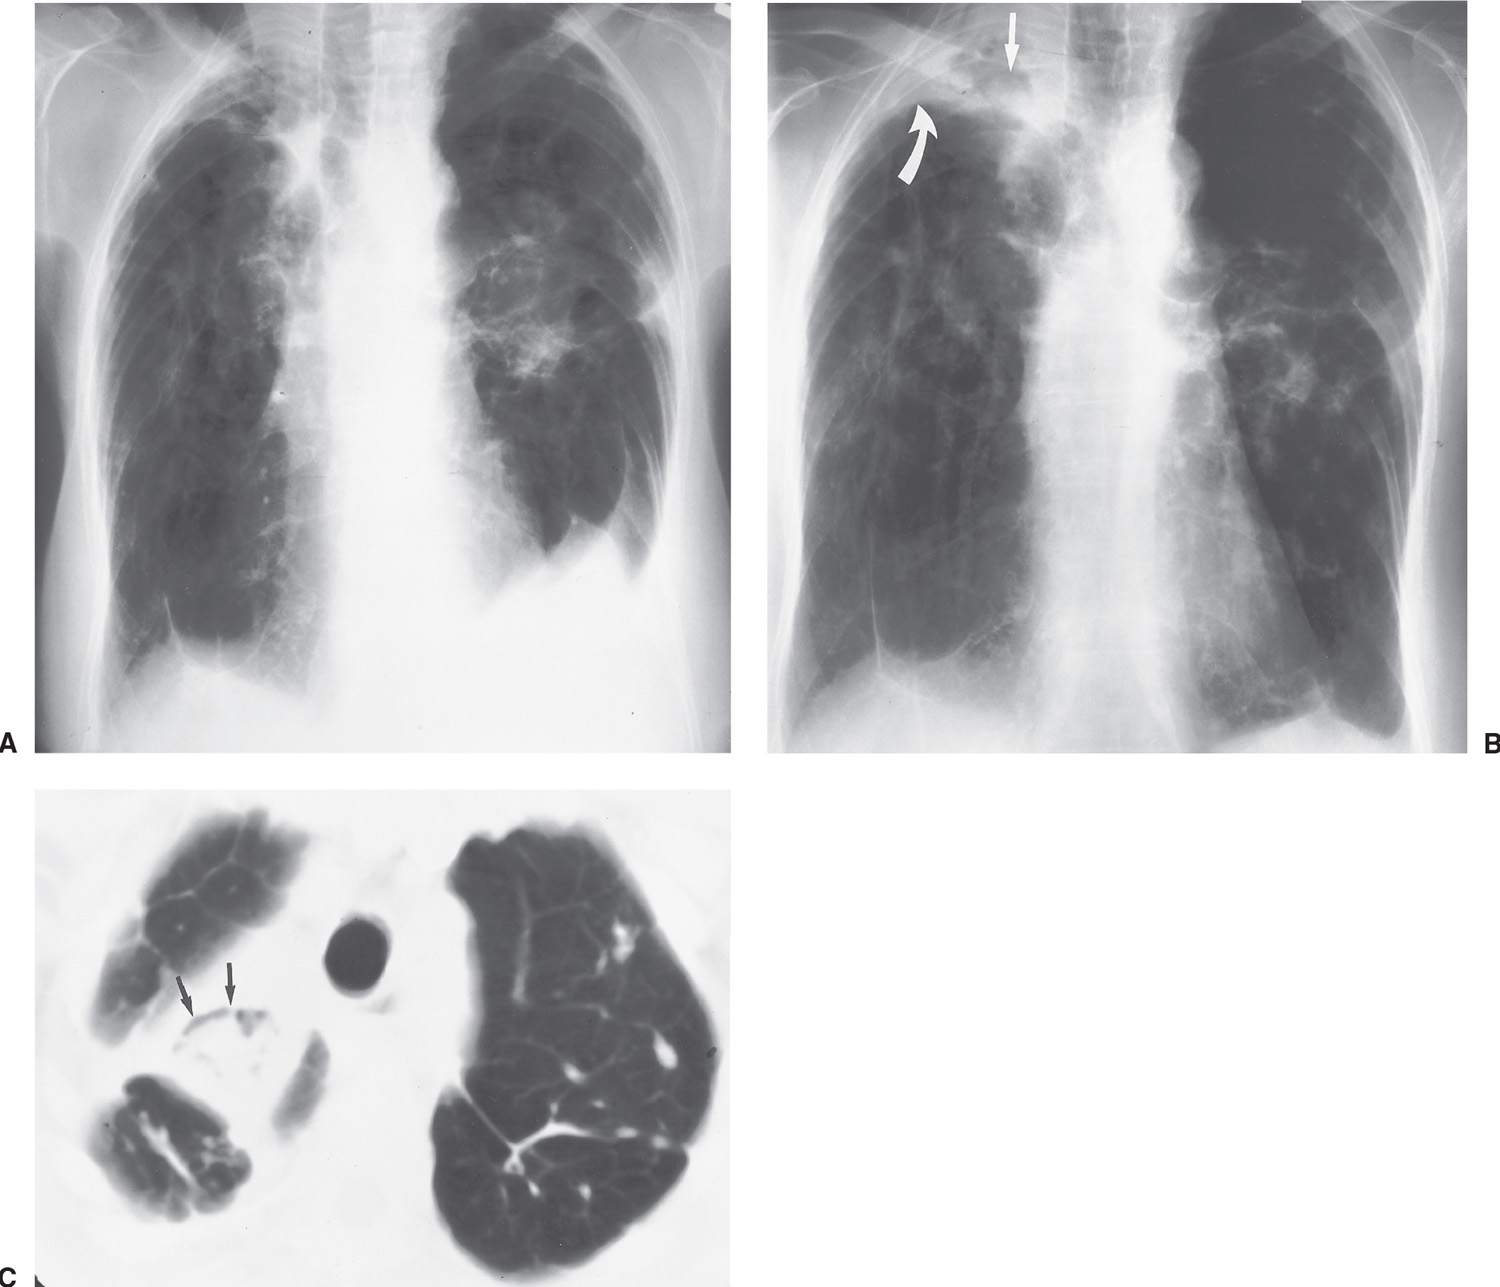

Визуализация и диагностика неинвазивного аспергиллеза с помощью КТ

Раздел: Необычные решения